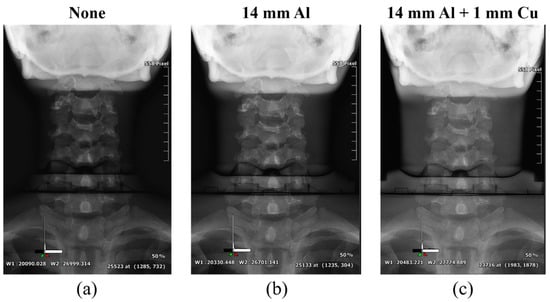

Figure 6, Figure 7 and Figure 8 show the acquired whole-spine AP, LAT, and long-leg AP X-ray images with and without additional filters, respectively. Visual evaluation of the obtained images confirmed that the image quality was improved when an additional filter based on Al and Cu materials manufactured with a 3D printer was used in thin areas such as the C-spine and ankle. In particular, the highest quality was observed in all the acquired X-ray images when a filter combining 14 mm thick Al + 1 mm thick Cu was used.

Figure 6.

Acquired whole-spine AP X-ray images without and with additional filters. (a) Whole-spine AP image (a) without an additional filter, (b) with a 14 mm thick Al additional filter, and (c) with a 14 mm thick Al + 1 mm thick Cu composite additional filter.